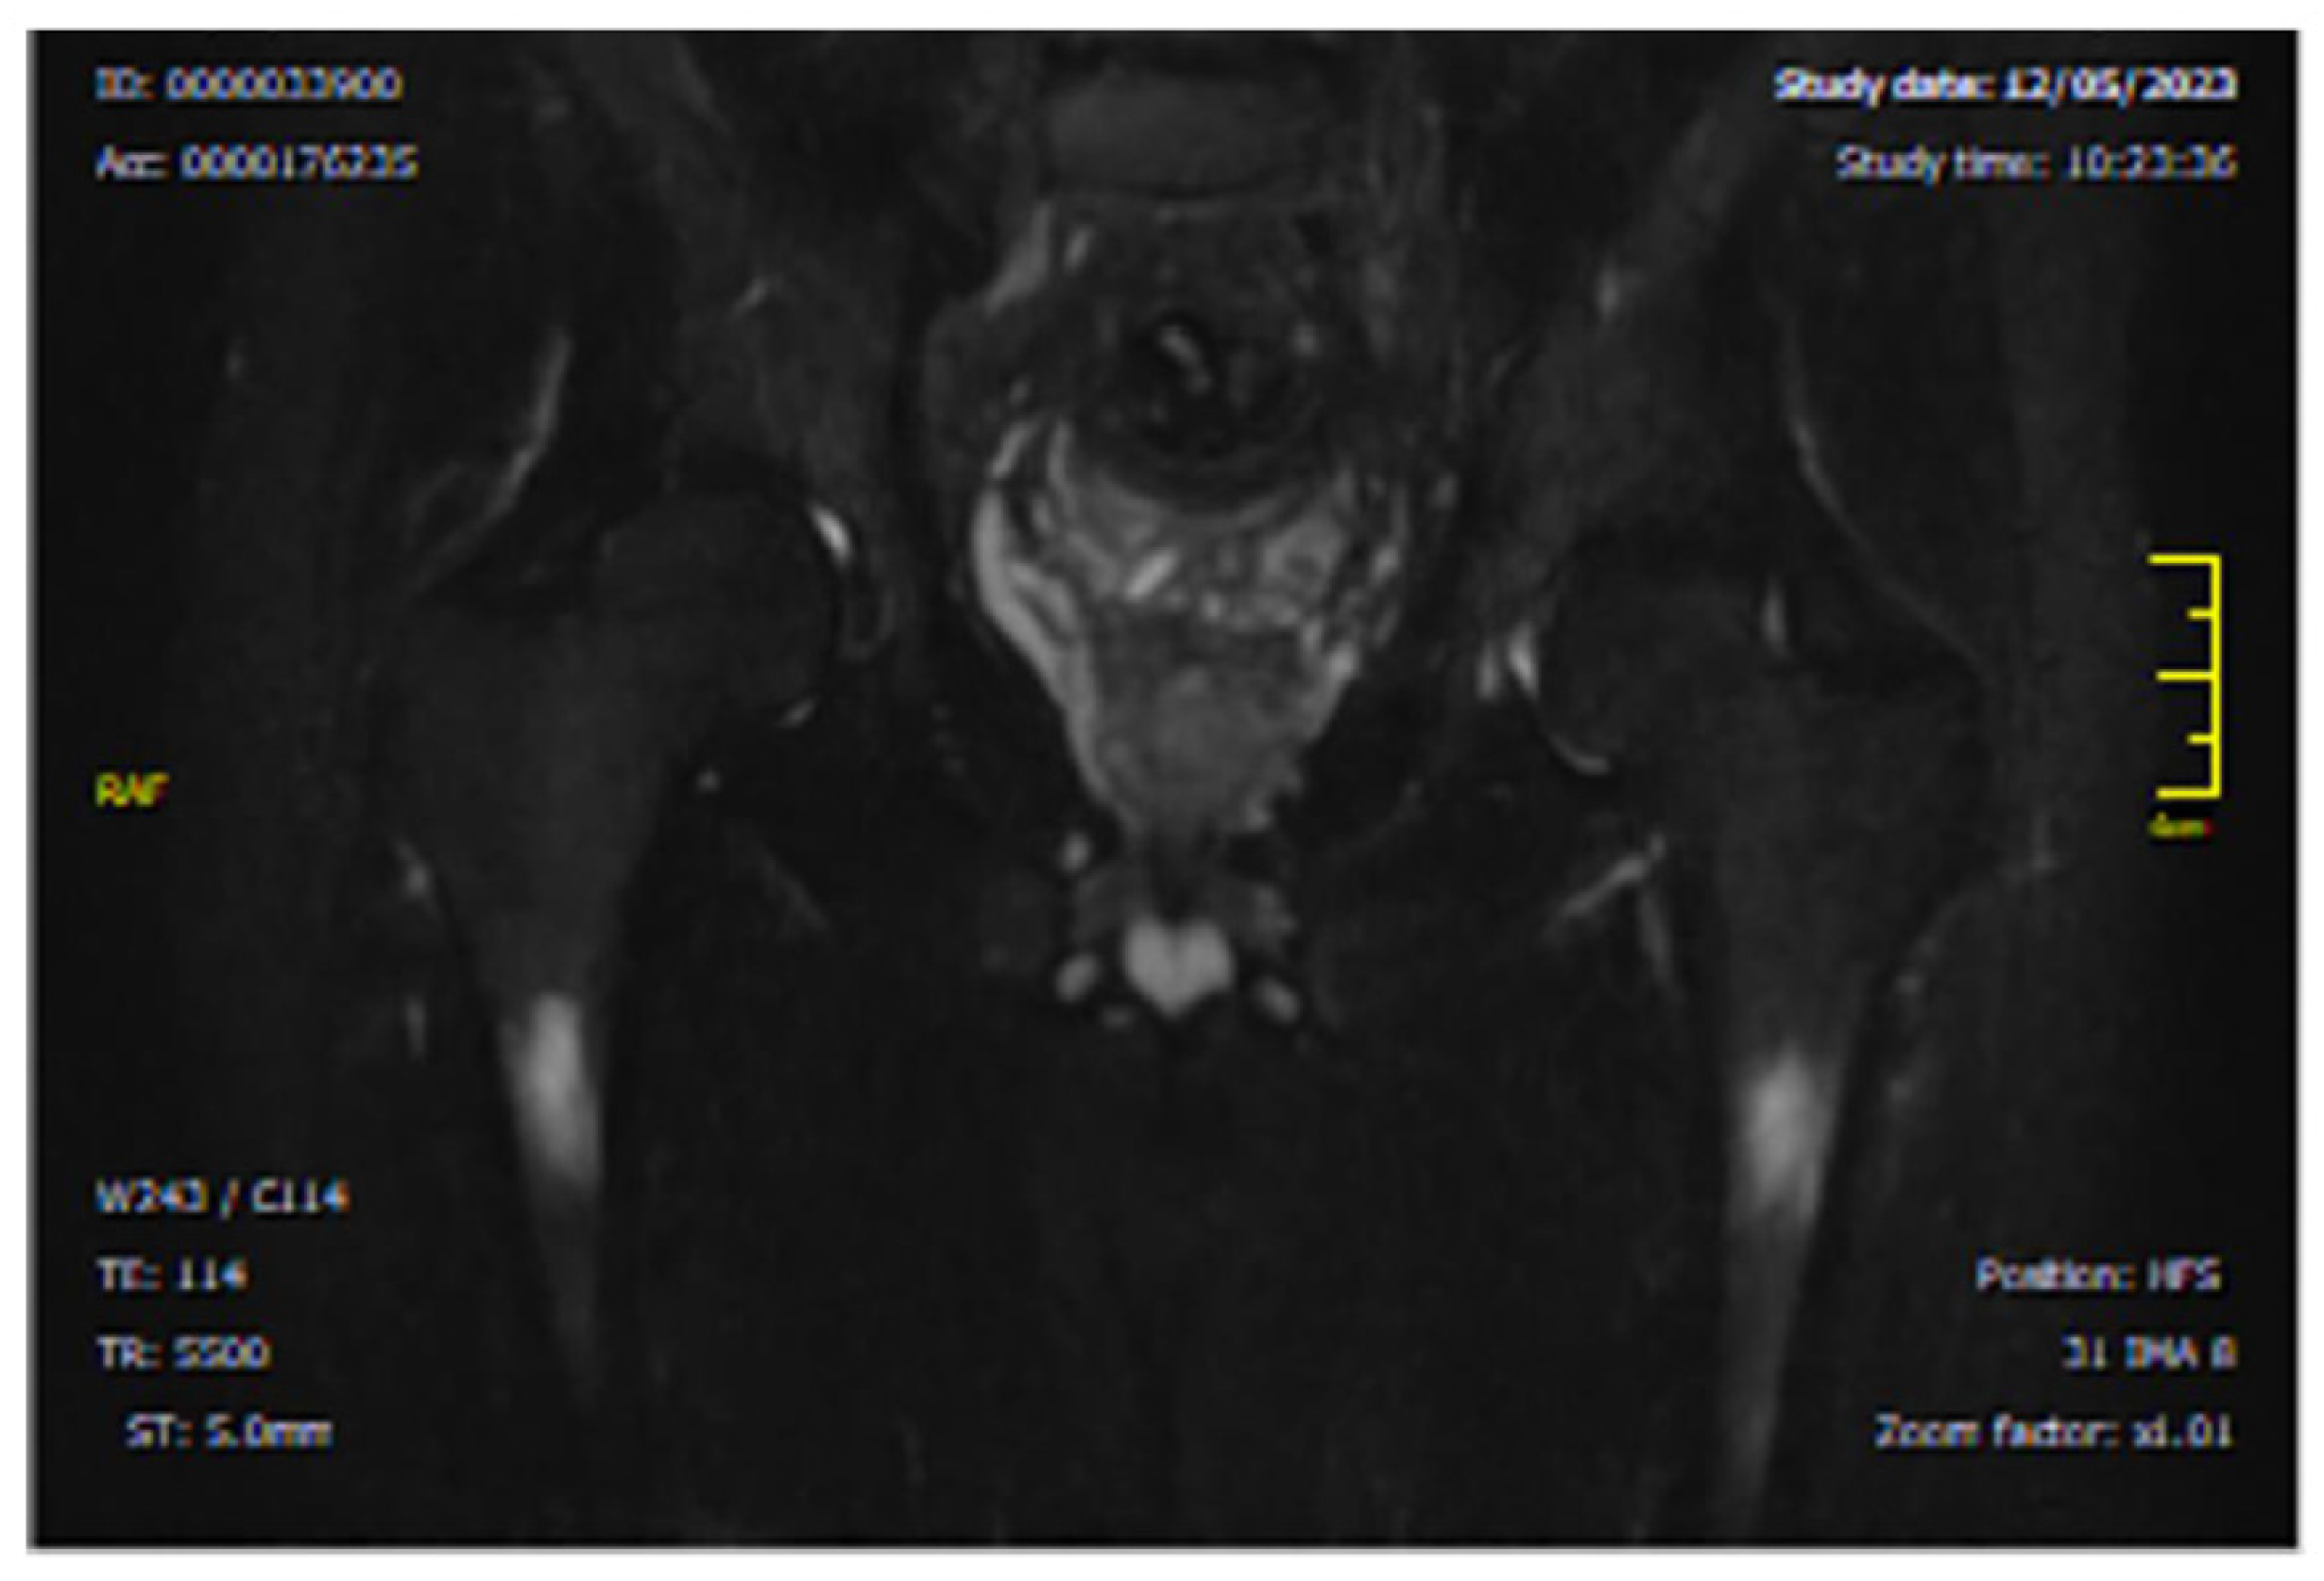

- CASE 1: A CML patient under dasatinib and imatinib treatment

- CASE 2: 60-year-old patient with imatinib therapy

- CASE 3: 66-year-old patient with imatinib therapy